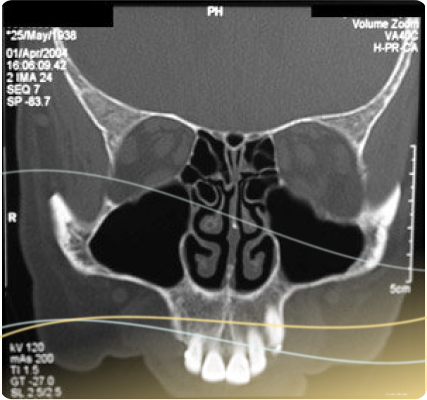

In-Office Low Radiation Sinus CT Scanner

Florida E.N.T. & Allergy offers the latest technology in sinus CT (computed tomography). The Mini CAT ™ is an in-office CT scan unit that offers precise imaging while offering reduced radiation as compared to a standard CT scan. We pride ourselves on our ability to offer our patients a high level of convenience and affordability when it comes to their imaging needs. In order to expedite your care, oftentimes the scan and followup visit can be coordinated the same day and our doctors review it with you immediately. We find this helps us explain the disease process and any future treatment planning that may be needed.

The CT scan works by utilizing a rotating x-ray device along with a digital computer to capture detailed cross-sectional and three dimensional images of body tissue. The machine captures these images in sections that resemble slices of bread, allowing clinicians to see the entire surface of a single section. Combined, all of these sections produce a 3-dimensional image. The Mini ™ device typically captures it’s imaging in as little as 20 seconds.

At CT scan can be very valuable in assisting your ENT surgeon in properly diagnosing your nasal and sinus problems. There are many diseases that can mimic sinus disease, and a CT of the sinuses can help narrow down the different options.